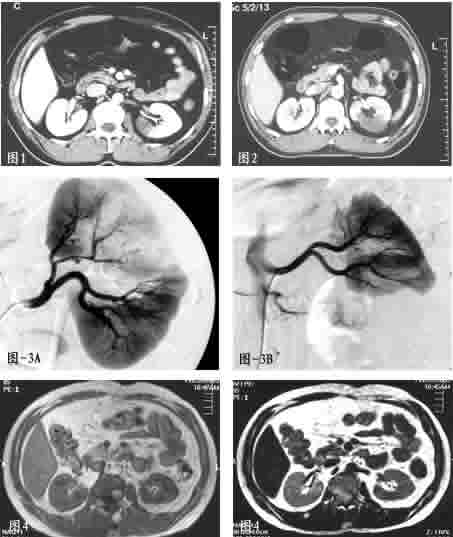

患者男性,40岁。因反复左腰部疼痛12天入院。患者入院前12天,无明显诱因出现左腰部剧烈疼痛,伴有明显腹胀。当时查体血压正常,左肾明显叩击痛,疑为肾结石。查尿常规正常,B超提示右肾下极见无回声区,造影剂增强CT检查显示左肾中极节段未见造影剂增强,考虑左肾梗塞(图1)。

患者于外院经低分子肝素抗凝及阿司匹林抗血小板等治疗5天,症状逐渐缓解并停药。停药后2天,患者再次出现腰痛、腹胀,伴血压升高130/100 mmHg;复查CT见肾梗塞灶扩大(图2)。患者起病后12天来我院就诊。